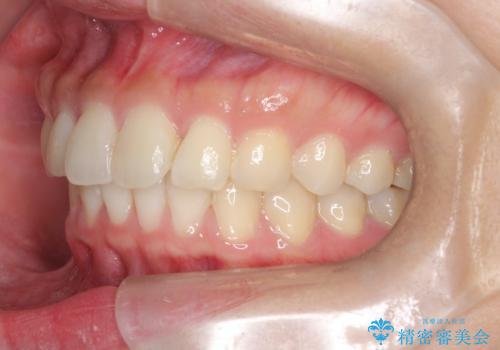

【インビザライン】翼状捻転+出っ歯を治したい

- 前歯の捻れと口元の突出を主訴に来院されました。

インビザラインを用いて上顎の遠心移動を行い、前歯を下げながら凸凹を綺麗に治すことができました。

歯を抜かない矯正治療を行う場合、口元は極端には変わりません。

今回は奥歯の遠心移動を行い、できる限り前歯を下げられるように治療を行いました。